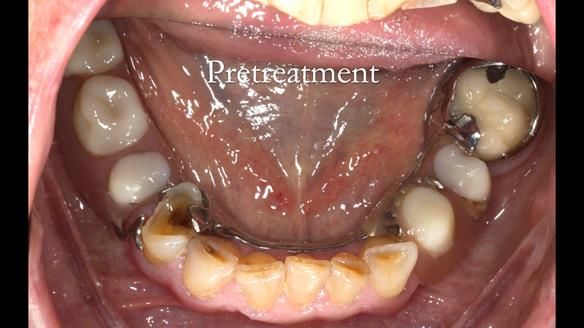

Diagnoses

- Missing teeth in the upper and lower jaws

- Upper and lower metal based RPDs, poorly fitting, worn occlusal surface, reverse curve aesthetics, lacking support

- Moderate to heavily restored dentition with deep overbite (Class 2 div II)

- Yellowish lower front teeth with small amount of wear.

- The lower right canine (LR3) is worn with MOD cavity.

- Decoronate post crowns upper right lateral and central incisors to use as over denture abutment supports

- Add upper right lateral and central incisor denture teeth to existing upper RPD as temporary measure during making of new RPDs

- Composite rest seats on the lower anterior teeth and reshaping existing crown

- Composite onlay lower right first premolar – designed to support new lower RPD

- New metal based upper and lower RPDs of Scandinavian design for improved, periodontal health, function and appearance.